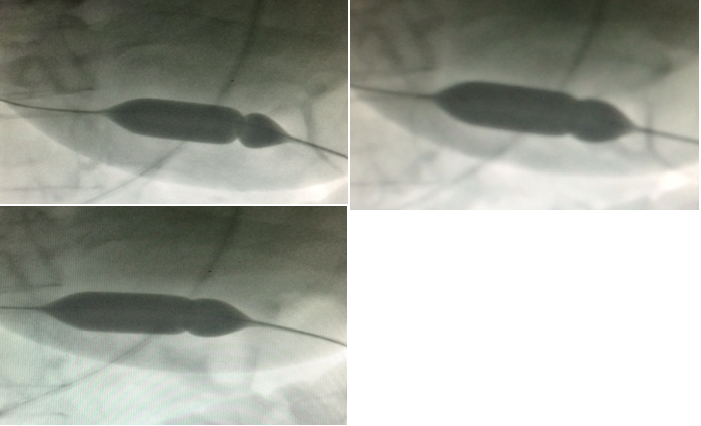

Фигуры